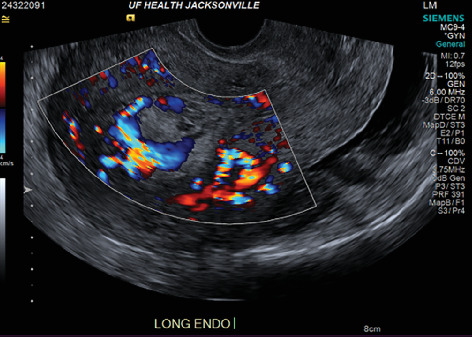

A placental polyp is a retained fragment of placental tissue that can lead to postpartum hemorrhage or become a nidus for infection. Hypervascular placental polyps can pose an increased risk of life-threatening postpartum hemorrhage requiring immediate intervention. Thus, prompt recognition and appropriate management are crucial in preventing maternal morbidity and mortality. Here, we present the case of a 29-year-old patient who had a spontaneous vaginal delivery at 36-week gestation after induction of labor due to pre-eclampsia with severe features. Quantitative blood loss at delivery was 1300 mL, and the patient received uterotonic medications. Due to continued bleeding, she underwent a suction curettage with clots and retained tissue removed from the uterine fundus. The total blood loss was estimated to be 4 L, and the massive transfusion protocol was activated. On postpartum Day 1, she underwent a bilateral uterine artery embolization; however, she developed further heavy vaginal bleeding. A second suction curettage was performed after ultrasound showed hypervascular material in the uterine cavity. The patient was subsequently discharged, but represented on postpartum Day 15 with increased bleeding. Imaging again demonstrated a hypervascular intrauterine polypoid mass. The patient desired definitive management and underwent a minimally invasive total hysterectomy.

胎盘息肉是残留的胎盘组织碎片,可导致产后出血或成为感染病灶。胎盘高血管性息肉可增加危及生命的产后出血的风险,需要立即干预。因此,及时认识和适当管理对于预防产妇发病率和死亡率至关重要。在这里,我们提出的情况下,29岁的病人有自然阴道分娩在36周妊娠引产后,由于先兆子痫严重的特点。分娩时定量失血量1300 mL,给予子宫强直药物治疗。由于持续出血,她接受了从子宫底取出血块和残留组织的抽吸刮除术。总失血量估计为4l,并启动了大量输血方案。产后第1天,她接受了双侧子宫动脉栓塞术;然而,她进一步出现大量阴道出血。超声显示子宫腔内有高血管物质后,行第二次吸刮术。患者随后出院,但产后第15天表现为出血增加。影像学再次显示一个高血管的子宫内息肉样肿块。患者希望得到明确的治疗,并接受了微创全子宫切除术。